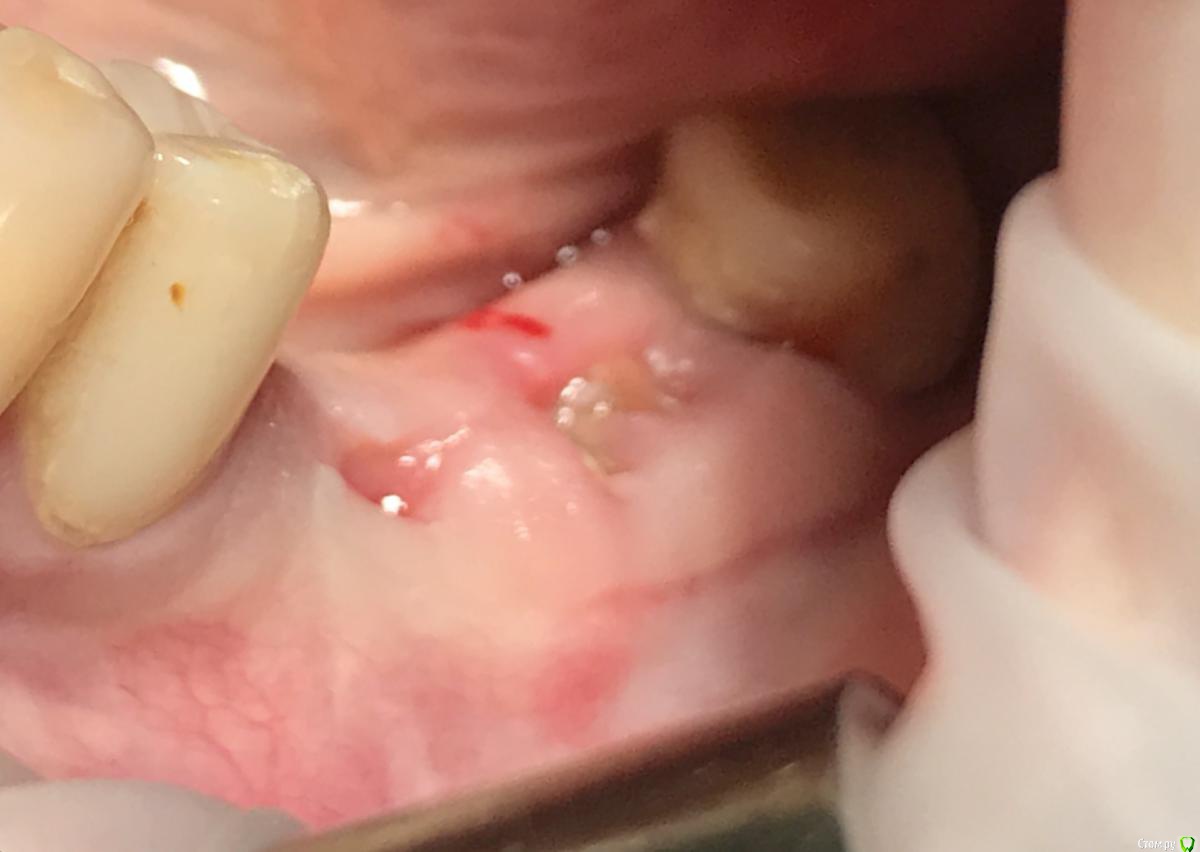

колесников Опубликовано 22 апреля, 2019 Поделиться Опубликовано 22 апреля, 2019 (изменено) И снова профайл спасает жизнь (облегчает жизнь имплантолога)Стандартная ситуация:36 периодонтит в стадии обострения с грануляциями,эксудацией,резорбцией компактной пластинки,дефицитом прикреплённой слизистой вестибулярного. Одна хирургия. Ноябрь 2018. Удаление,кюретаж,имплант Astra tech profile 4.5x9 под заглушку,торк около нуля. Вестибулярного сст,консервация графтом Sureoss 0,5 чипс с APRF,закрытие шайбой по Ноймайеру. Через неделю шайба несостоятельна-удалена. Пациентка созрела на удаление 37го. Выполнена декоронация в связи с отъездом пациентки,далее через 2 недели удаление и имплантация 37го. Промежуточный осмотр в январе. В марте установлены формирователи . Апрель контрольный осмотр. Периотест -5. Направлена на протезирование. Изменено 22 апреля, 2019 пользователем колесников 4 Ссылка на комментарий